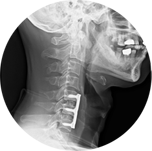

當頸椎被固定融合後該節椎間盤上下兩節椎骨融合為一,頸椎少了一個活動的關節,必需由鄰近節椎間盤增加活動度來代償,若有多節的手術情況更為嚴重,幾年後常有「鄰近節病變」的發生,即上下節的椎間盤因工作量增加較容易退化、突出,讓患者再度產生神經壓迫,症狀復發,甚至需要再次椎間盤切除手術治療。人工椎間盤(圖六、七、八)即是近年來科技進步的產物,在切除病變的椎間盤後,用人工椎間盤植入此空隙,藉以保留此病變節脊椎的活動度,可降低鄰近節病變的產生。

人工椎間盤在2006年台灣衛生署核准開始使用,經過十多年的使用經驗效果很好,確實可降低鄰近節病變的產生,多年來價格一直沒下降,目前我們使用的最新一代的Prodisc C vivo (圖九),此產品裝置容易,可以明顯降低手術的風險及縮短手術時間,又不用戴頸圈,但一個是25萬5千元。雖然在2021年12月起C4-5及C5-6可以向健保局申請,但由於經費有限、條件很嚴格,能申請通過給付的很少,申請條件請查臉書 "陳建良神經外科"。

圖六

圖七

圖八

圖九